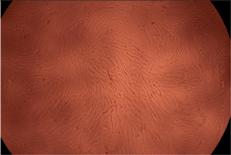

| Sample | Micrographs | ||

|---|---|---|---|

| 24 h | 48 h | ||

| Control |  |  | |

| F127 | 10 µg/mL |  |  |

| 50 µg/mL |  |  | |

| 100 µg/mL |  |  | |

| 200 µg/mL |  |  | |

| F127/PA = 10/1 (g/g) | 10 µg/mL |  |  |

| 50 µg/mL |  |  | |

| 100 µg/mL |  |  | |

| 200 µg/mL |  |  | |